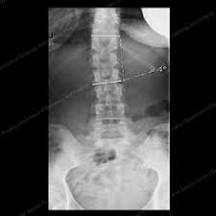

Personal HealthJane Brody on health and aging. I’m not a sedentary person. In my 30s and 40s, I was a runner, and for decades, I played singles tennis three or more times a week. After a back injury in my late 30s, I took up swimming and cycling. Now, in my 70s and with artificial knees, I walk or cycle and swim laps daily, all of which has kept me aerobically fit, free of pain, reasonably trim and energetic. So in combing recently through the professional literature on exercise and bone health, I was quite disappointed to learn that neither swimming nor cycling is especially good for my bones — at least, not the ones most susceptible to fracture. Swimming, in fact, might compromise the strength of those bones because it lacks the tug of gravity. That’s what researchers have found when they measured bone mineral density in young athletes who swim or cycle, and even in some who run. There are two reasons for this. One is the continuous nature of these activities. Bones, it seems, don’t like constant pressure.

They respond better to exercise that involves forceful muscle contractions, occurring in starts and stops and with some variety — as happens, for example, when playing tennis or training with weights. To maintain strength, bones also need the stress of gravity, which is lacking in cycling and swimming and not as powerful when walking as it is when running.